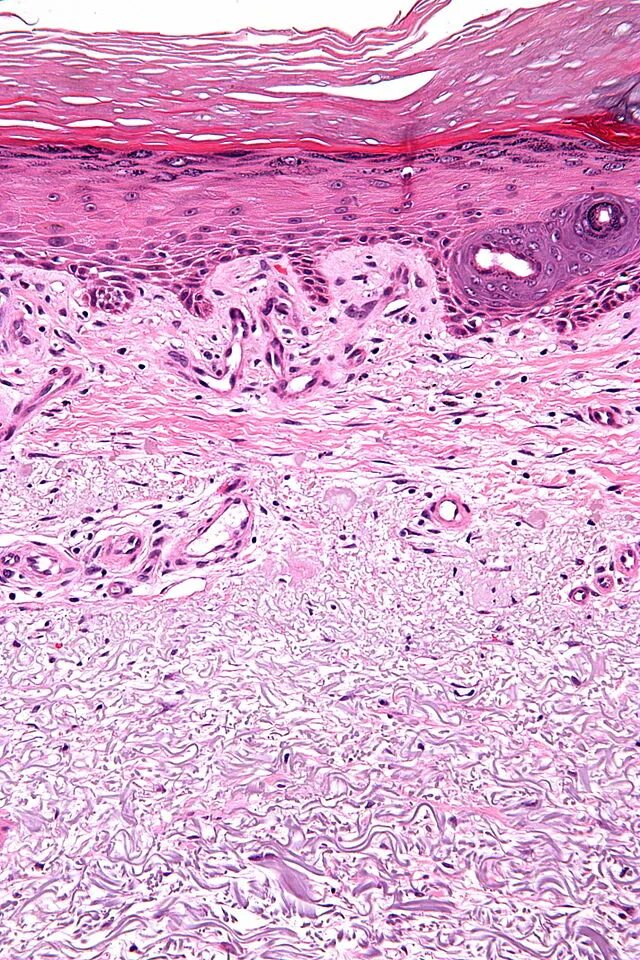

Солнечный эластоз